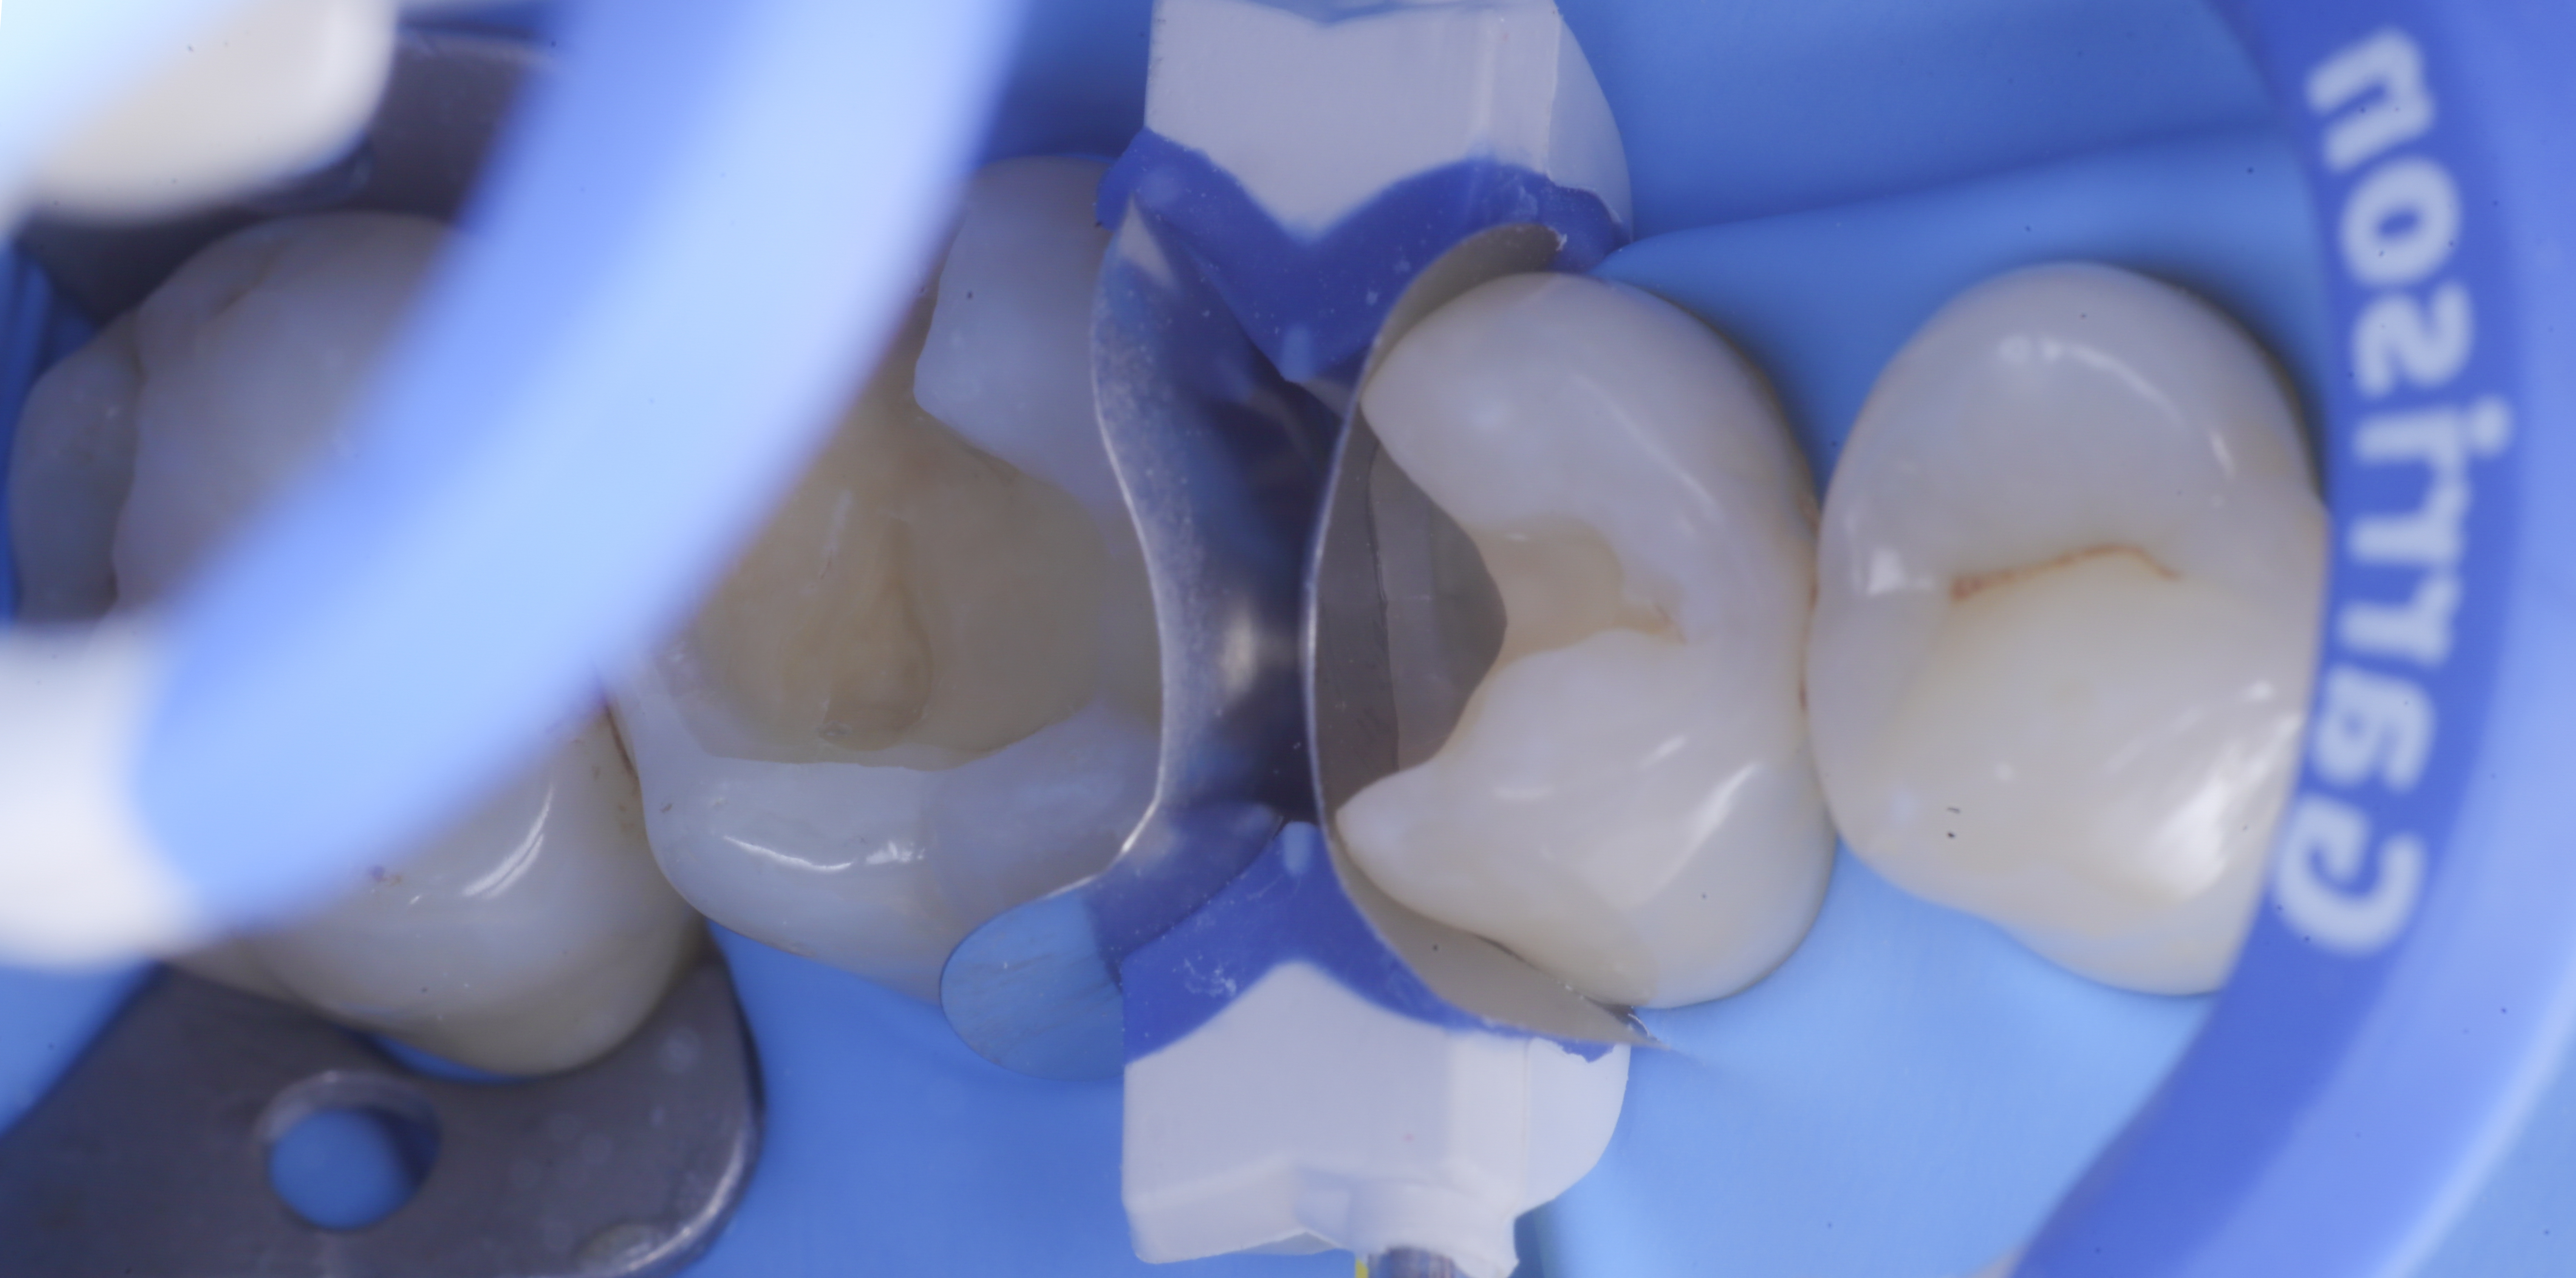

foto 4 Aspetto della chiusura cervicale e sulle pareti assiali dato dalla prima matrice

foto 5 Aspetto della chiusura cervicale e sulle pareti assiali della seconda matrice